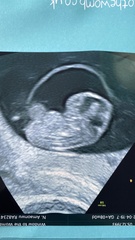

Got myself in a flap because my RHR dropped massively and my symptoms were disappearing already. But had my early scan today and everything is fine thank god 😍 measuring ahead at 8+5.